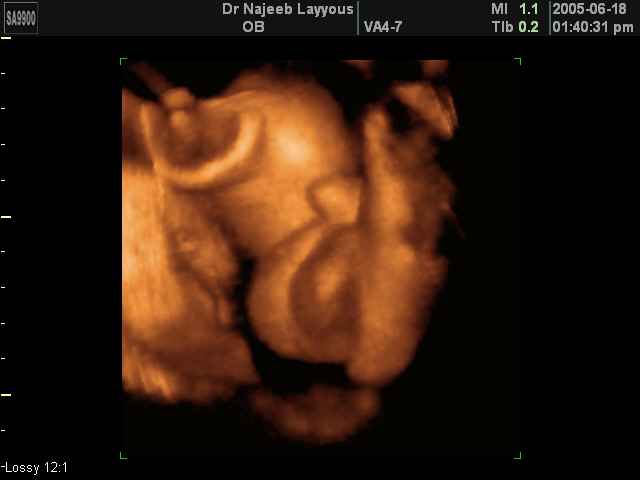

- 3D Photos échographie des parties du fœtus